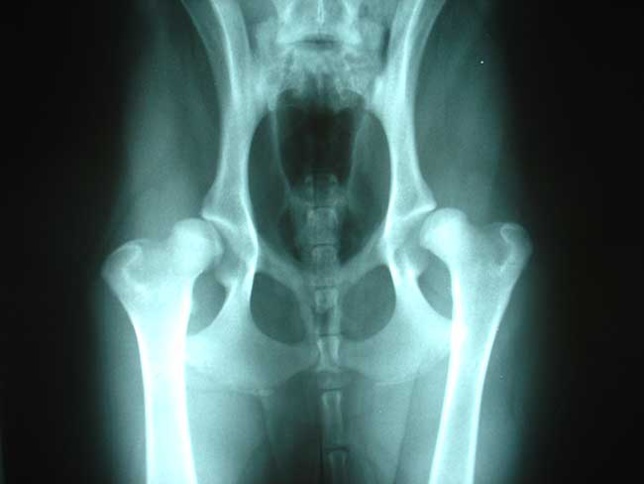

Dans le traitement des vertiges d’origine cervicale, l’ostéopathe tentera de favoriser la mobilité des différentes structures cervicales et thoraciques (muscles, ligaments, articulations) dans le but de restaurer la mobilité de ces structures. L’ostéopathe agira également parfois sur les entrées posturales comme les pieds et les chevilles ainsi que sur les articulations de la mâchoire. En effet, ces structures participent à la proprioception, fonction physiologique qui renseigne le cerveau sur la position, l’équilibre et les mouvements du corps.